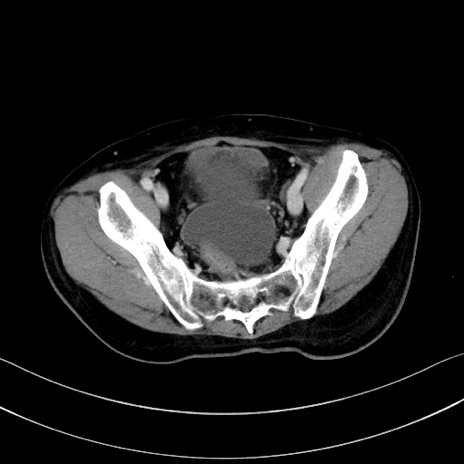

症例28(横断像)

【症例】60歳代男性

【現病歴】胃癌にて胃全摘後。食思不振が悪化し、夜中に嘔吐することがある。

【既往歴】胃癌、胃全摘、脾摘、胆摘後

【データ】WBC 5900、CRP 10.56